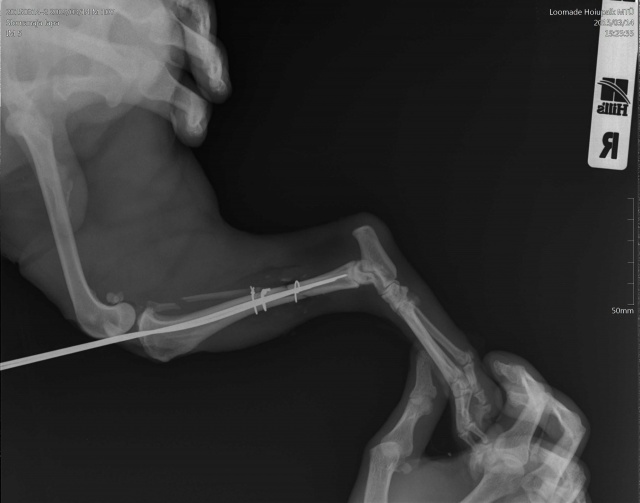

Koer on opereeritud.

Tagumise käpa luumurd.

Koerake sattus varjupaika vigastatud käpaga. Ülevaatusel selgus, et koera käpal on mitmekordne luumurd. Pidime paigaldama ka kateetri, kuna ta ei saanud pissida (ilmselt autolöögist põhjustatud kusepõie atoonia).

Собака поступила в приют с множественным переломом ноги. Не могла пописать (видимо был удар машины и, как результат, атония мочевого пузыря). Нога в очень тяжёлом состоянии, и завтра мы кладём собаку на операционный стол.